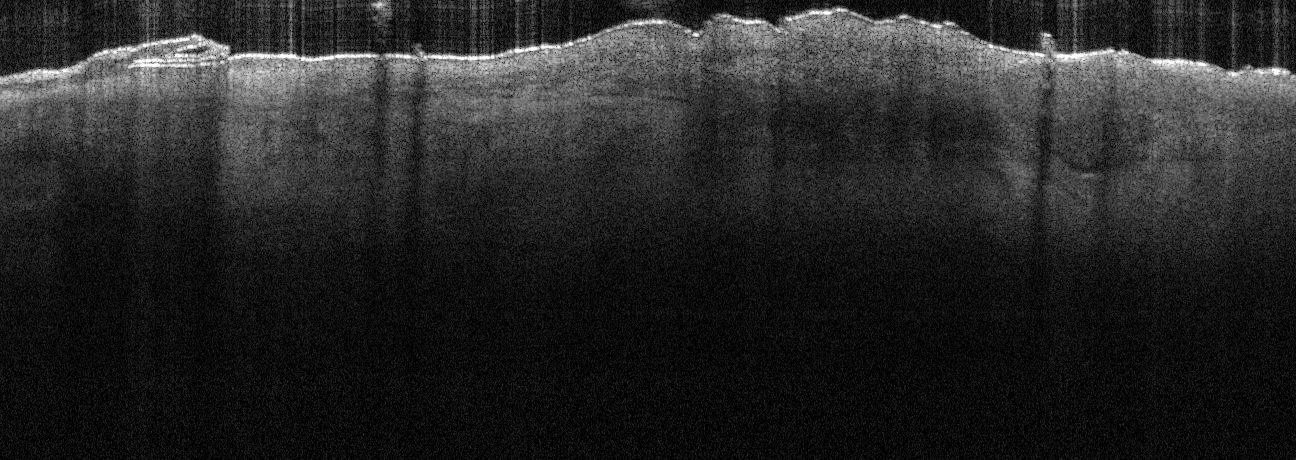

- Peripheral boundary in superficial types is always more prominent on dermis facing side of nest

- DEJ alteration is always prominent in superficial nests

- Dermis protruding growth of the basal layer disrupts the expected undulating pattern of the DEJ

- DEJ often appears darker in areas where nests present

- Nests can sometimes be easily identified by a distinct lower cleft region appearing like a horseshoe, underlining the nest

- Larger more established nests often have areas of areflectivity at their core

- This areflective core is due to tissue fluid from the central necrosis that occurs in some basal nests